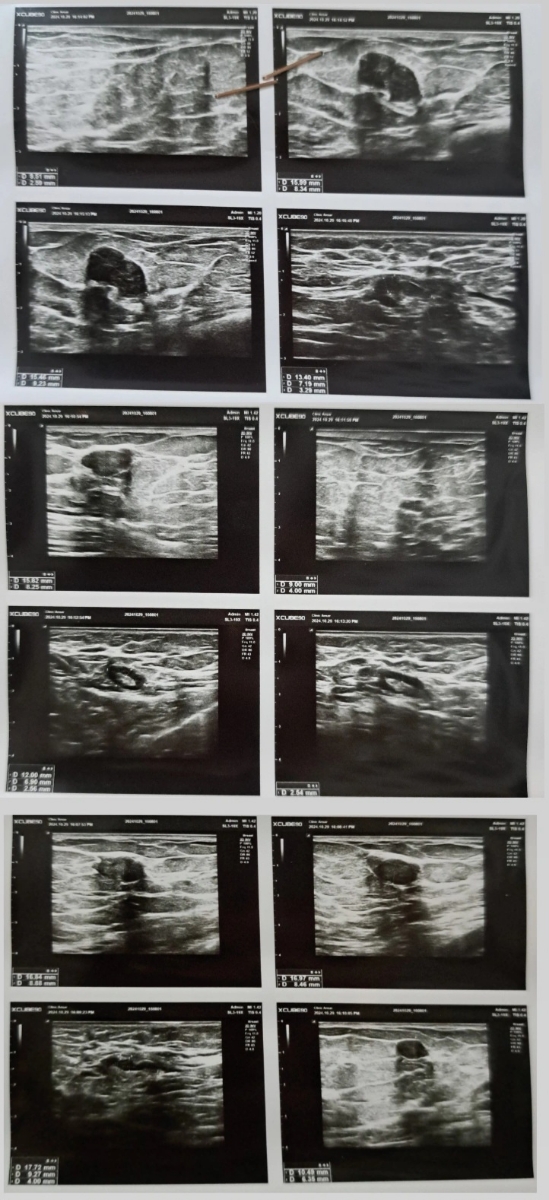

و یه سونو سینه هم انجام دادم چون قبلا توده فیبرو آدنوما داشتم ولی سه سال گذشته و چک نکرده بودم.

سونو سینه

شیرین جانم بالاخره درست شد درمورد سونوگرافی سبنه بذار اول صحبت کنیم، ببین درکل خداروشکر اصلا شواهدی به نفع بدخیمی نداری خب؟ ولی غدد لنفاوی ت تحریک شدن که میتونه به دلایل ساده مثل استفاده از مام و یا سرماخوردگی اخیر و... باشه مراجعه کن جراح پستان ، لمس کنن اگر نیاز میبینن آنتی بیوتیک بدن و بعد اتمام دوره درمان مجددا سونوگرافی پیگیری بده این مورد رو حتما حتما پیگیری کن